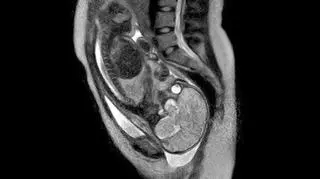

Niezwykły moment narodzin dziecka zarejestrowano za pomocą skanera MRI. Rodząca kobieta w Niemczech podczas porodu była poddawana rezonasowi magnetycznemu. Niezwykłe zdjęcie opublikował serwis newsscientist.com

To pierwsze zdjęcie w historii wykonane skanerem używanym do rezonansu magnetycznego zrobione podczas samego porodu.

Jak tego dokonano? Położne w berlińskim szpitalu odbierały poród kiedy matka leżała w skanerze. Otwarta konstrukcja urządzenia pozwoliła lekarzom na dostęp do matki i dziecka, a jednocześnie zarejestrowała podróż noworodka przez drogi rodne.